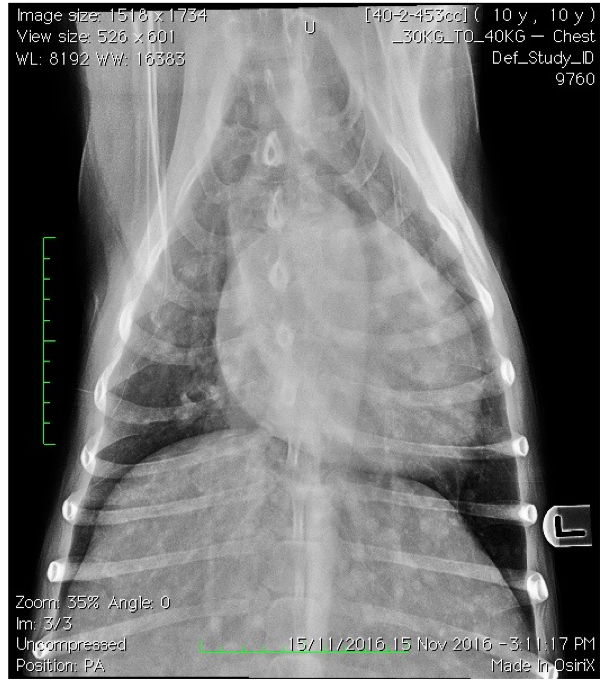

Q

Which lung pattern is shown here?

A

Nodular interstitial pattern

This is associated with metastatic lung tumours.